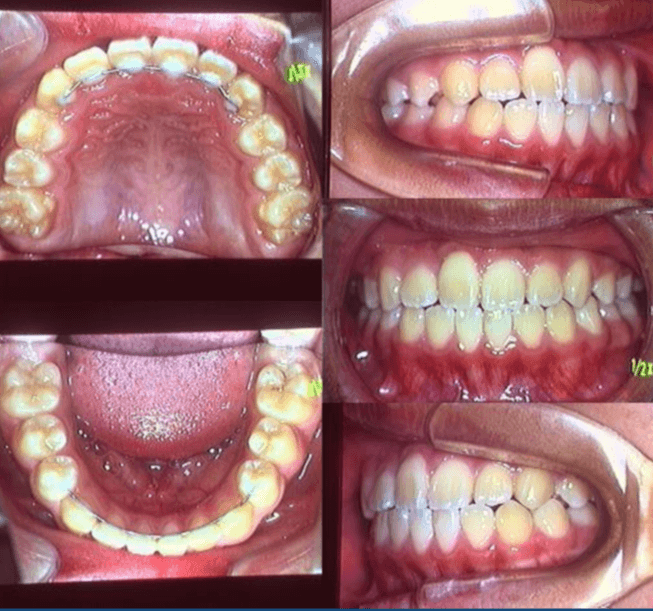

| 年齢・性別 | 8歳9ヶ月の女児 |

|---|---|

| 主訴 | 歯並びの乱れを気にされて来院された患者様です。将来的なスペース不足と歯のねじれ(翼状捻転)が懸念されました。 |

| 治療期間・回数 | 2年10ヶ月・19回 |

| 費用 | 430,000円(税別) |